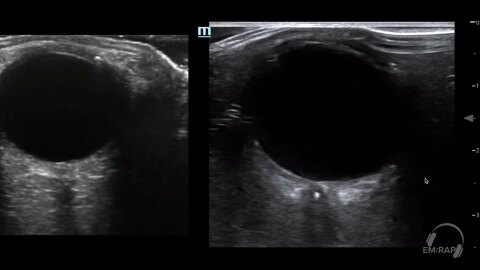

Optic Nerve Sheath Diameter

1 chapterJuly 2024